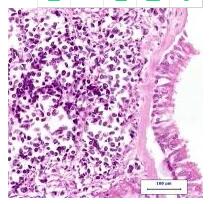

CT引导检是非诊断性的。 手术探查显示,由于纵隔侵袭和出血而无法切除的小细胞癌(图4)。 患者开始用卡铂

/依托泊苷

进行缓解化疗,在第2天和第3天口服依托泊苷治疗。她完成了这个化学疗法的四个周期,并且总体上耐受性良好。

图4